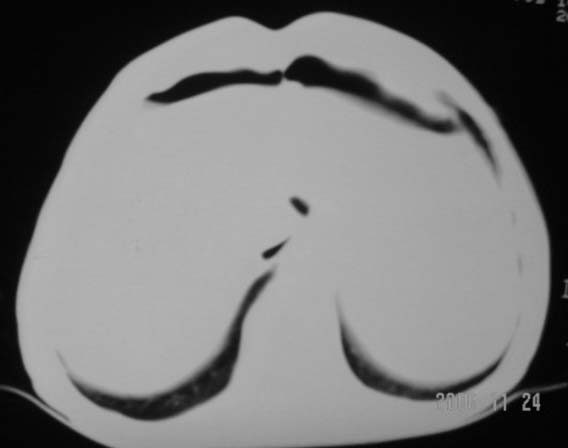

仰卧位见:肝前间隙及肝脾间隙内可见新月形气体密度影,边缘清楚,侧卧位见气体随体位改变而移动,ct值约-929hu。膈下、肝下间隙及部分肠间隙可见液性密度影。考虑:1、上腹部空腔脏器穿孔,以胃穿孔可能性大。2、少量腹水。

仰卧位见:肝前间隙及肝脾间隙内可见新月形气体密度影,边缘清楚,侧卧位见气体随体位改变而移动,ct值约-929hu。膈下、肝下间隙及部分肠间隙可见液性密度影。考虑:1、上腹部空腔脏器穿孔,结合临床,首先考虑胃穿孔可能性大。2、少量腹水

肝前间隙及肝脾间隙内可见新月形气体密度影,边缘清楚,侧卧位见气体随体位改变而移动,

支持消化道空腔脏器穿孔(腹腔内大量游离气体影,小网膜囊内亦见气体影),少量腹水。